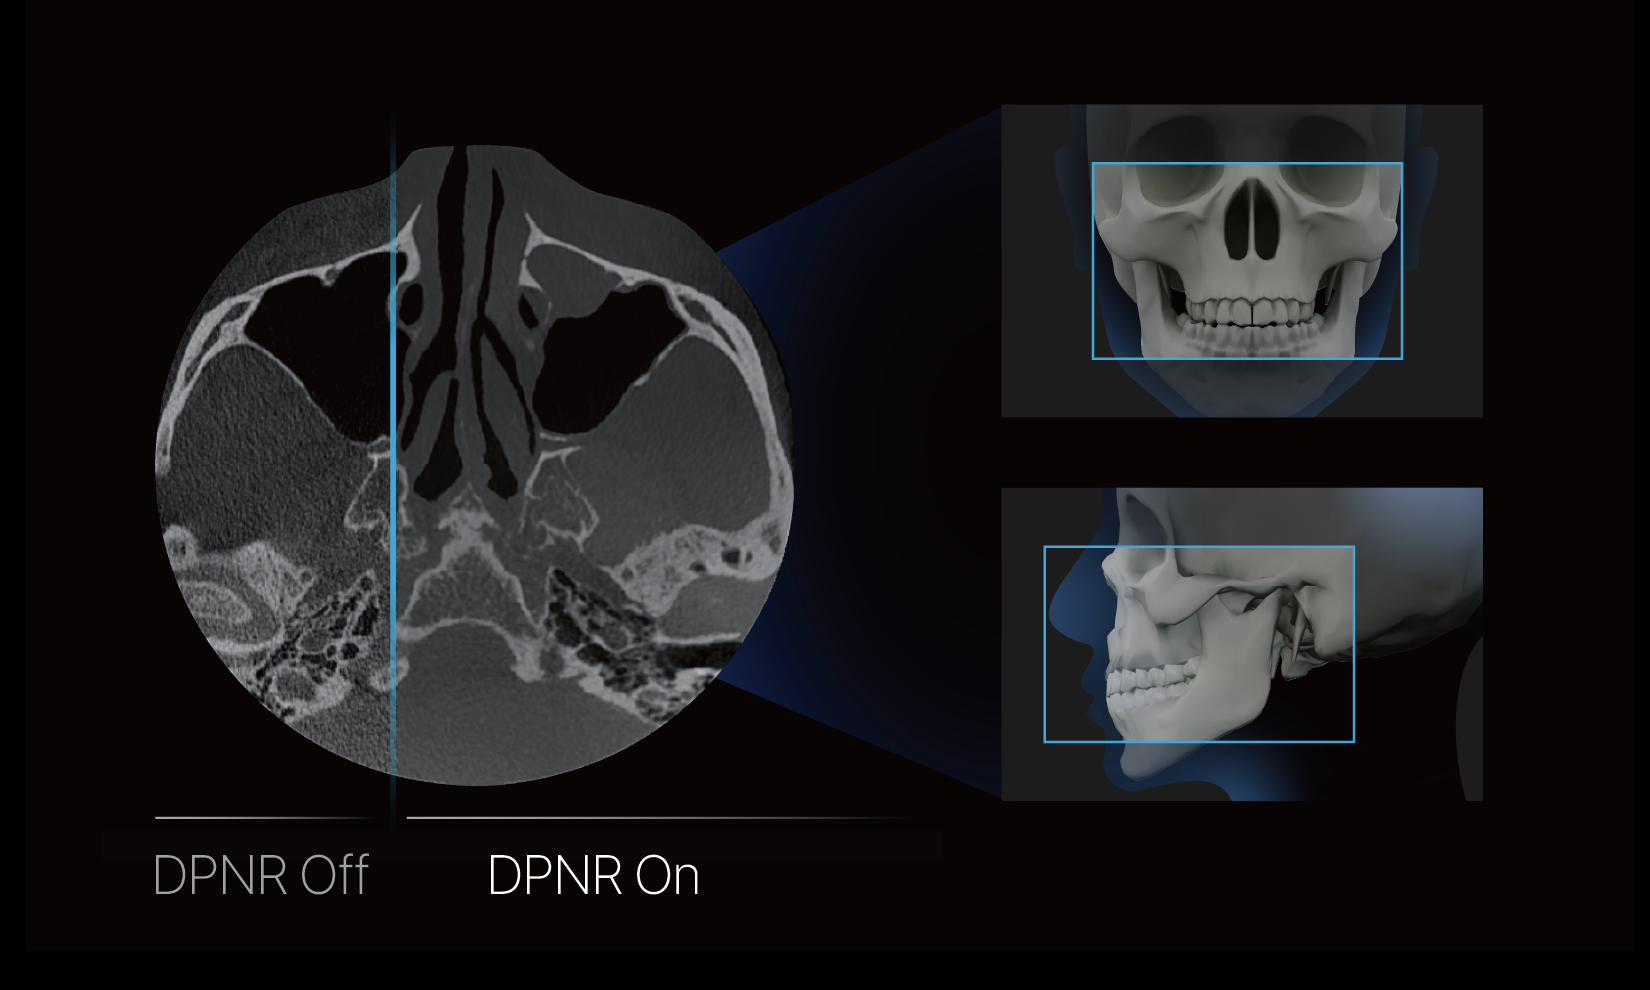

High-resolution imaging: Detail Preserving Noise Reduction

RAYQuantum’s DPNR technology effectively reduces CBCT noise, enhancing the clarity of anatomical structures and making interpretation and analysis easier.

High-resolution imaging: Detail Preserving Noise Reduction

RAYQuantum’s DPNR technology effectively reduces CBCT noise, enhancing the clarity of anatomical structures and making interpretation and analysis easier.